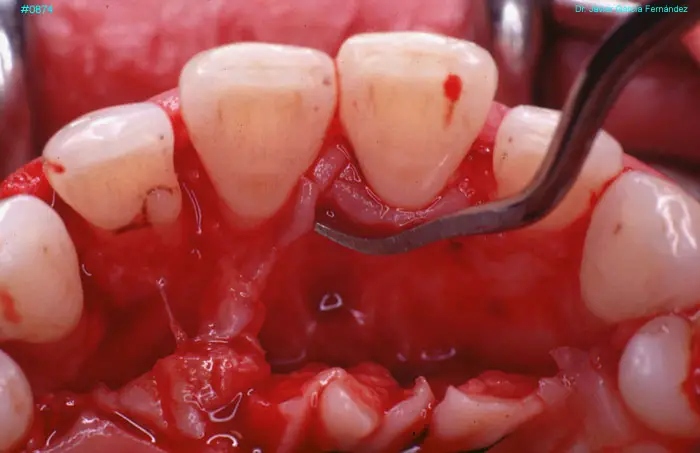

Atlas of Surgical Techniques in Periodontics. Chapter III. Atlas de Técnicas Quirúrgicas en Periodoncia